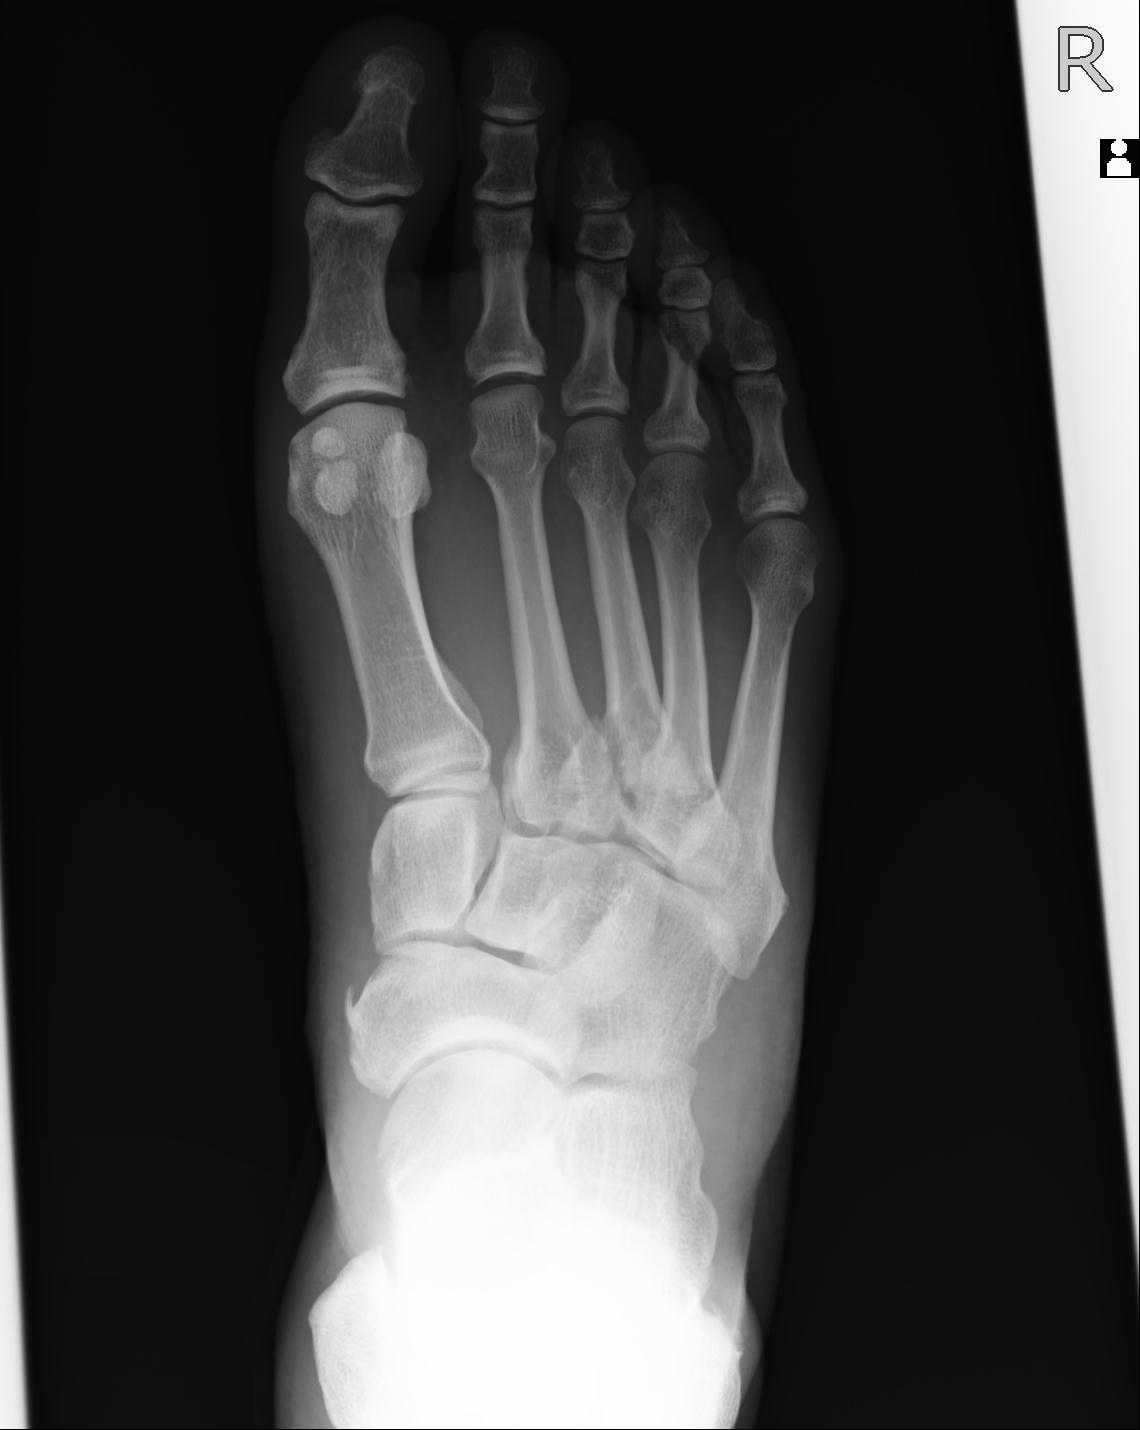

56476 8/28 4R 1/21 2R 左足関節 デジカメ写真 72歳女性 右足関節AS